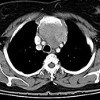

МРТ молочной железы. Послойное сканирование органов грудной клетки с помощью радиочастотной энергии в сильном магнитном поле. Это позволяет проводить неинвазивное исследование легких, плевры, органов средостения, тканей молочной железы и очищать данные от других инструментальных методов визуализации (рентген, КТ молочной железы). МРТ молочных желез наиболее полезна для диагностики поражений легких и средостения и оценки их проникновения в окружающие структуры. МРТ может обнаружить поражения лимфатических узлов (с лимфогранулематозом, туберкулезом, метастазированием ), Патологическое развитие органов, патологию брюшной аорты (аневризма, диссекция), экссудативный плеврит и перикардит При наличии показаний МРТ органов грудной клетки выполняется с контрастным усилением.

МРТ грудной клетки используется для оценки состояния легких, плевры, органов и тканей средостения (трахеи, пищевода, кровеносных сосудов, лимфатических узлов, тимуса, жировой ткани), а также мышц и тканей. подкожная жировая клетчатка Диагностическая ценность МРТ при исследовании легочной ткани зависит от типа патологии, многие заболевания лучше или с той же точностью, что и при сканировании. МРТ грудной клетки менее информативна при исследовании ребер и грудины, но иногда успешно используется для выявления новообразований костной и хрящевой структур, для диагностики травматических повреждений и аномалий развития.

В онкологии МРТ молочной железы проводится при диагностике рака легких, рака плевры, опухолей реберной ткани и грудины (остеомы, хондромы, остеобластокластомы и ), Злокачественных и доброкачественных новообразований средостения. Кроме того, МРТ грудной клетки можно использовать для выявления метастазов из опухолей других участков ткани легкого и для оценки участия лимфатических узлов в злокачественных новообразованиях органов грудной клетки и некоторых других онкологических процессах (например, лимфогранулематозе). Во время процедуры определяется топология новообразования, прорастание соседних анатомических структур подтверждается или исключается. Этот метод редко используется врачами, так как более рентабельная компьютерная томография для диагностики туберкулезных процессов в легочной ткани не уступает МРТ молочной железы. Однако иногда исследование используется для выявления изменений в средостенных лимфатических узлах. Сосудистые хирурги назначают МРТ для выявления врожденных аномалий и приобретенных патологий сосудов средостения.